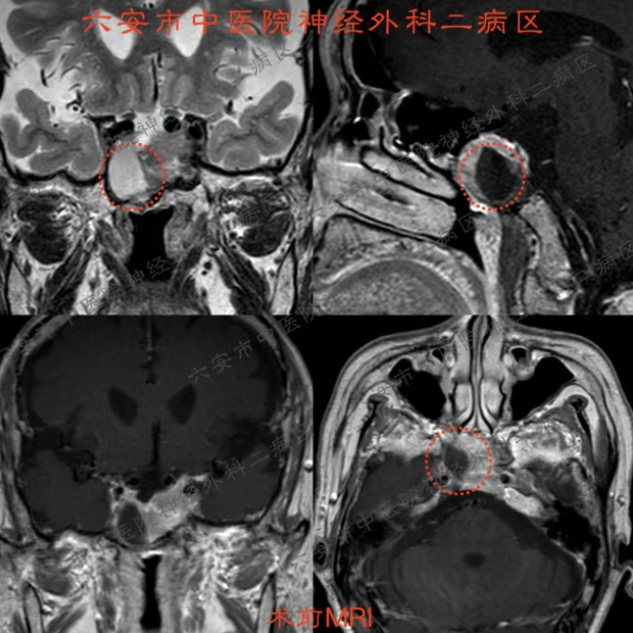

章大爷平时身体还算硬朗,就是有十多年的高血压。这次头痛,他本以为只是鼻窦炎老毛病犯了,便在耳鼻喉科门诊做了个磁共振。没想到,检查结果却让全家人心头一紧——在他的“鞍区”发现了一个占位性病变,高度怀疑是垂体瘤。

这个位置虽小,周围却都是“要害”,紧挨着视神经、脑部大血管和内分泌中枢。瘤子虽大概率是良性的,但如果放任不管,可能会越长越大,压迫神经导致视力下降甚至失明,还会影响全身内分泌功能。

手术中,在内镜的清晰视野下,病变组织被精准切除,周围的视神经、重要血管保护完好。术后,章大爷没有出现任何并发症,恢复非常顺利。头痛消失了,视力、感觉、活动一切正常。住院观察几天后,各项指标平稳,他满意地办理了出院。